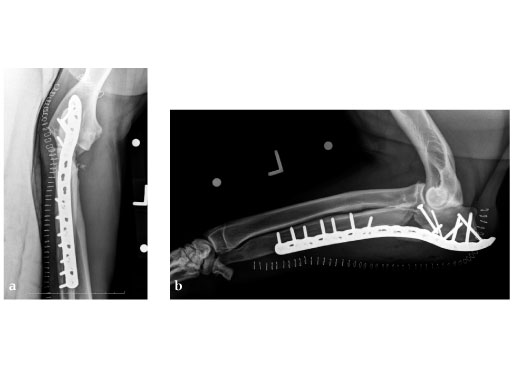

LCP Broad Plate 3.5

The LCP 3.5 broad plate is indicated for long bone fractures in large breed dogs.

This plate is similar to the standard human LCP, except for a central, stacked combination hole at one end, designed to facilitate treatment of metaphyseal fractures.

The LCP broad plate 3.5 system includes 14 plates with lengths ranging from 7 to 22 staggered holes. It can be used with 3.5 mm cortical screws (either locking head or standard) as well as 4.0 cancellous bone screws. This offers greater versatility than conventional plates. The implant material is 316L stainless steel. The plates are housed in the small fragment plate set graphic case. No additional instruments or screws are needed.

5-year-old male English Mastiff, road traffic accident.

(Case provided by Michael P Kowaleski, North Grafton, USA)